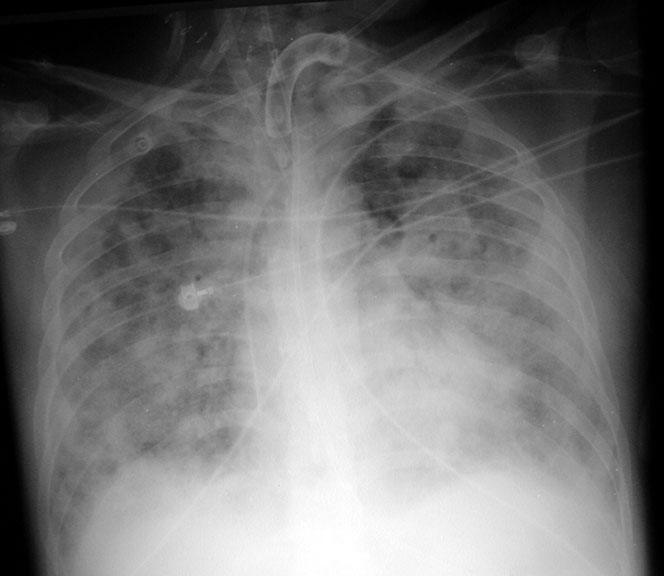

The patient was admitted to the intensive care unit where he received broad spectrum antibiotics and fluids. Exam and pulmonary artery catheter measurements were consistent with sepsis syndrome. His oxygenation progressively deteriorated and he became increasingly confused necessitating intubation. Chest x-ray demonstrated diffuse ground glass pulmonary infiltrates. CT scans of the head, chest, abdomen and pelvis were performed and were unremarkable except for diffuse bilateral pulmonary infiltrates. The infectious disease consultant was concerned about possible thrombotic thrombocytopenic purpura and the patient was transferred to LUMC for possible plasmapheresis.

CXR        CT Chest      (A new window will open to show x-rays. Close window to return to the case)